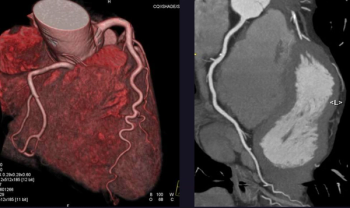

Cardiac CTA before transcatheter aortic valve replacement can be used to better determine risk by assessing left atrium functional parameters that are predictive of mortality.

Patients suspected of having coronary stenoses may benefit from ultra-high-resolution CT, according to a recent study that showed high diagnostic confidence in severely calcified coronary atherosclerotic disease.